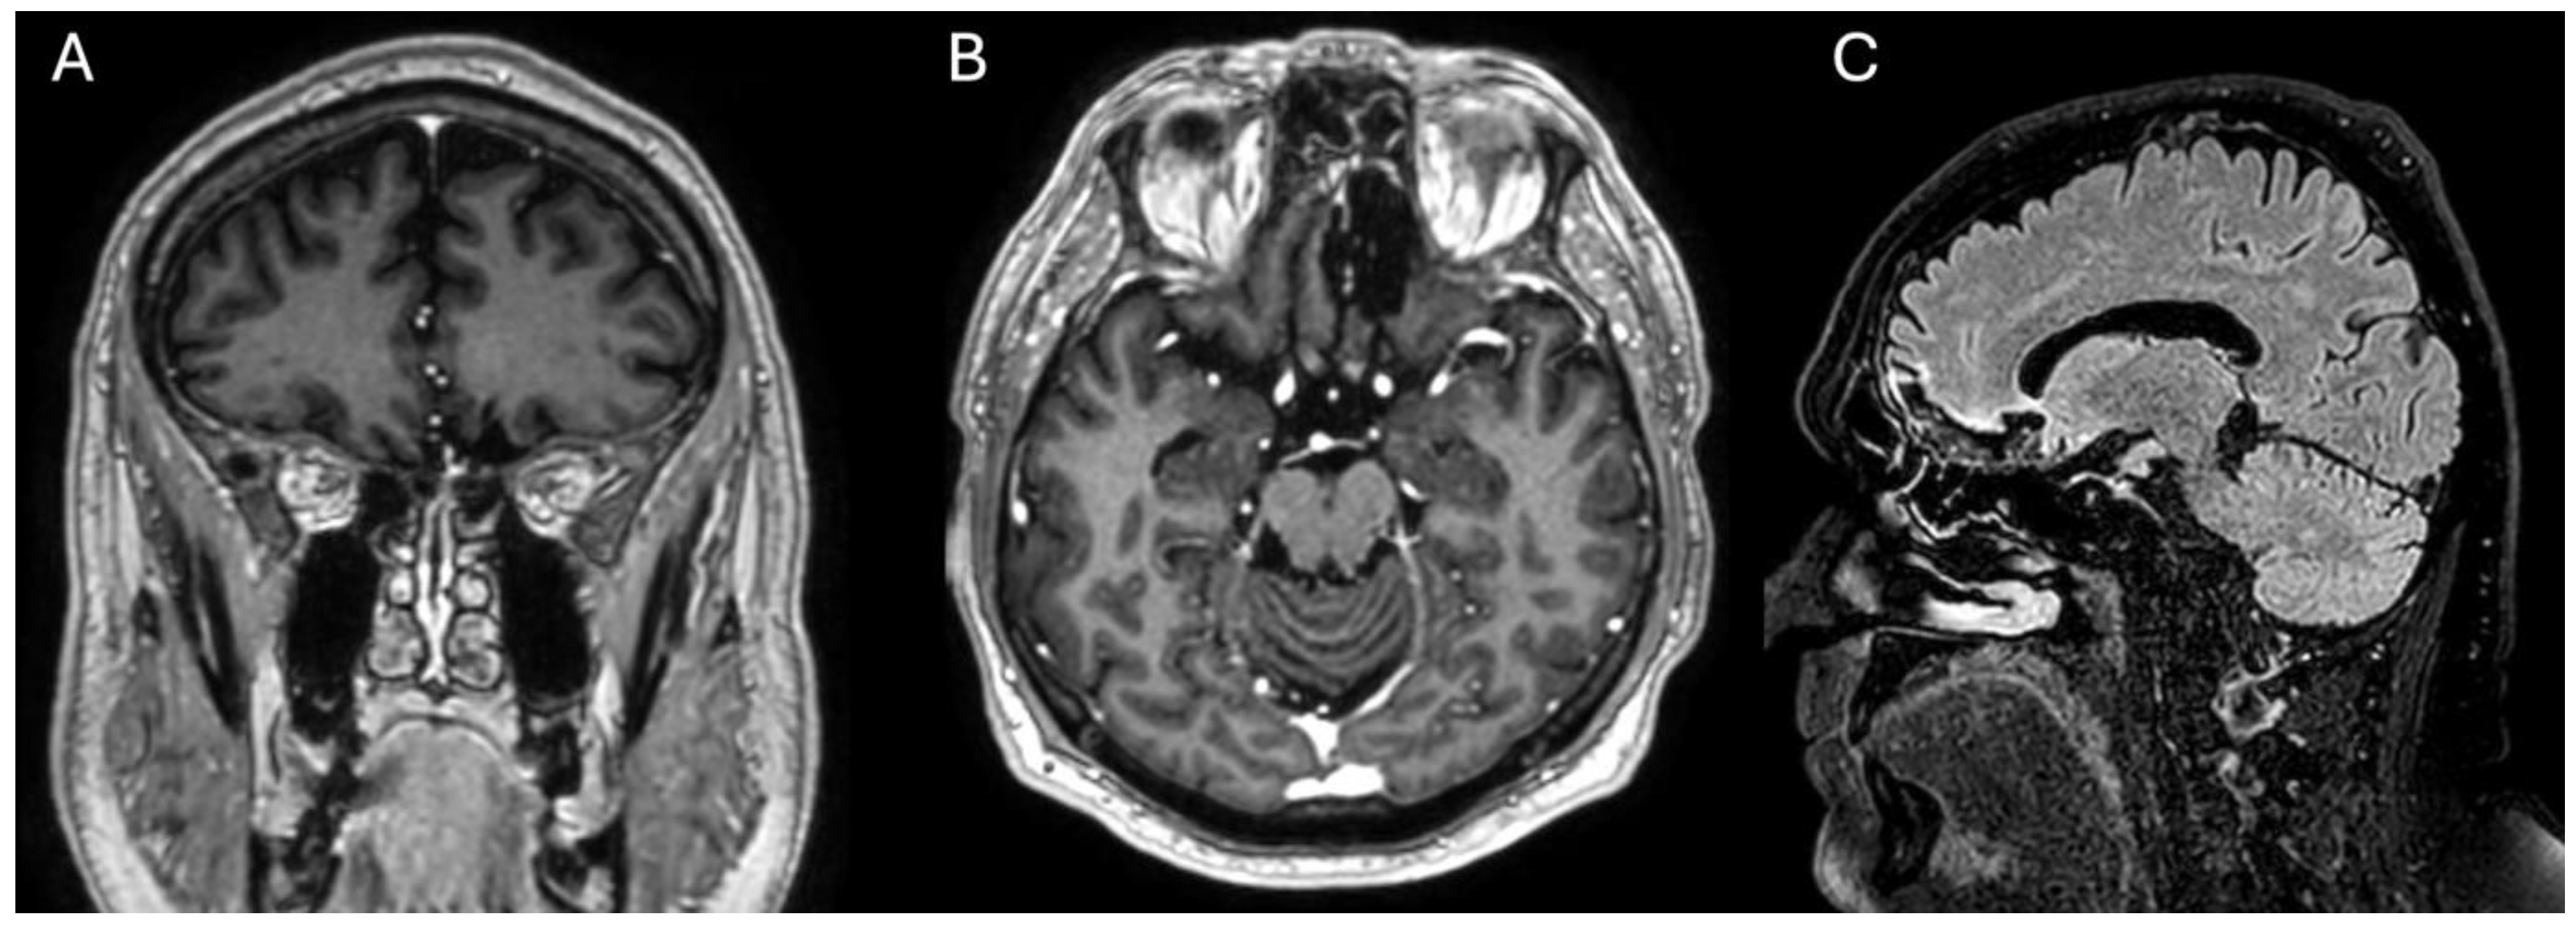

2.3. Postoperative Period and Follow-Up